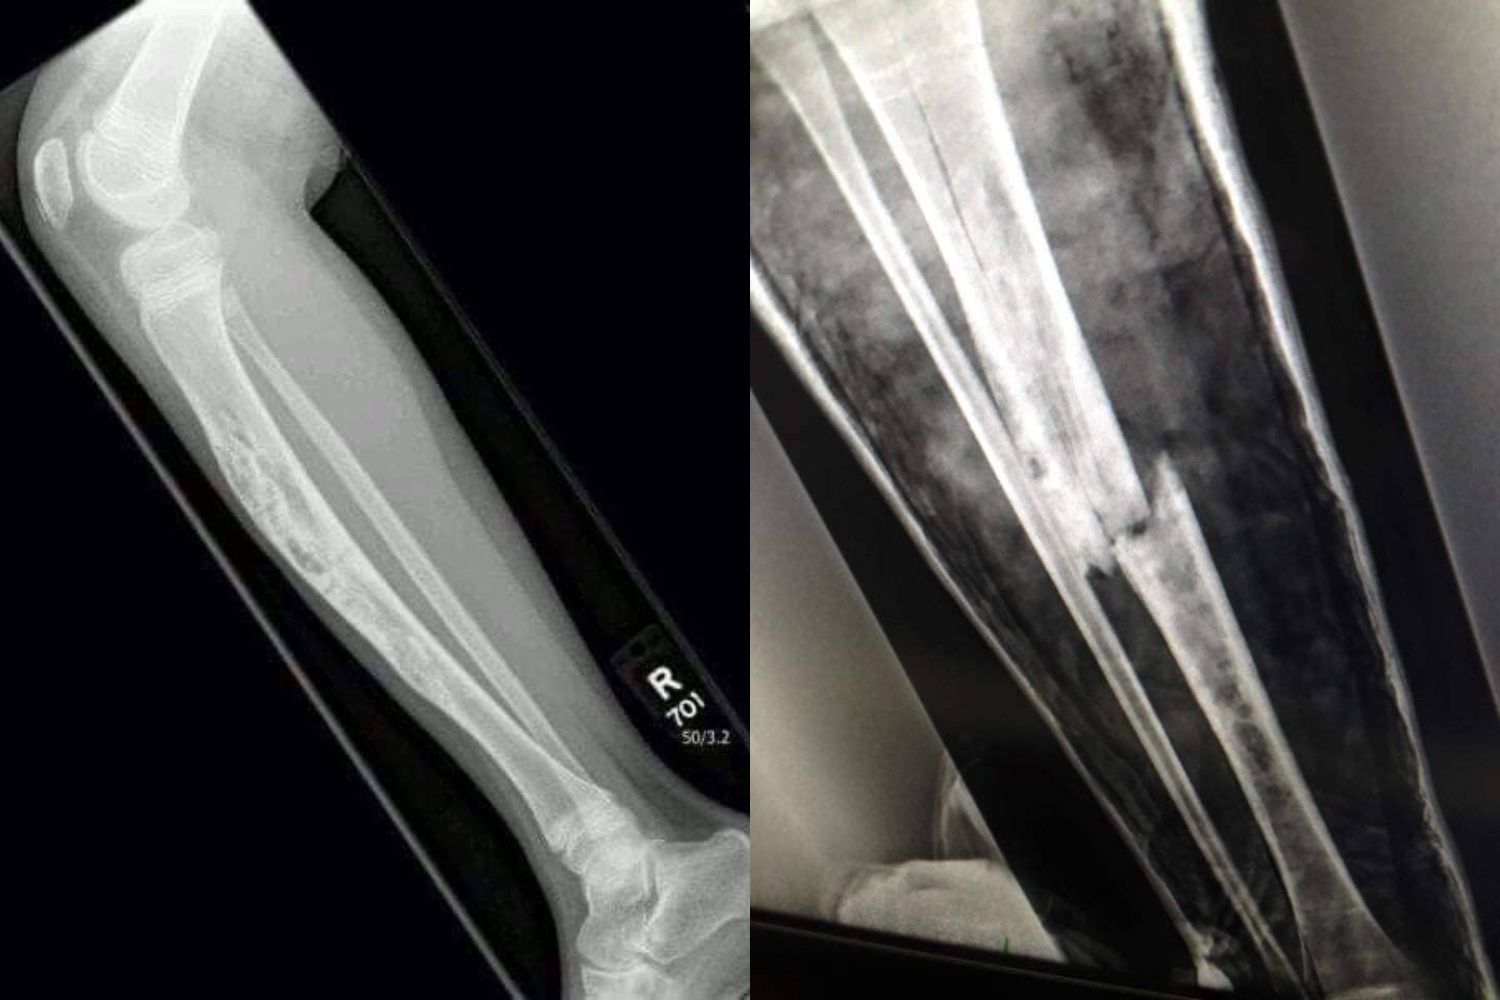

When I was 8 years old, I was diagnosed with a rare bone cancer called adamantinoma after a freak incident in my garden. While the cancer was confined to my right leg, it meant the bone was extremely fragile and that I couldn't bear weight on it.

In 2013, I started secondary school. By this point, the volume of my hospital appointments had dropped significantly, and doctors had determined that the only long-term option would be to amputate my leg. However, that decision would be mine to make somewhere down the line.

A sound I had been taught to fear my entire life. I knew instantly… I had broken my diseased leg.

After an emergency trip to A&E and repositioning surgery a few days later, I was told the break was so severe that I would never walk again. I became bedbound, confined to a hospital bed in my living room.